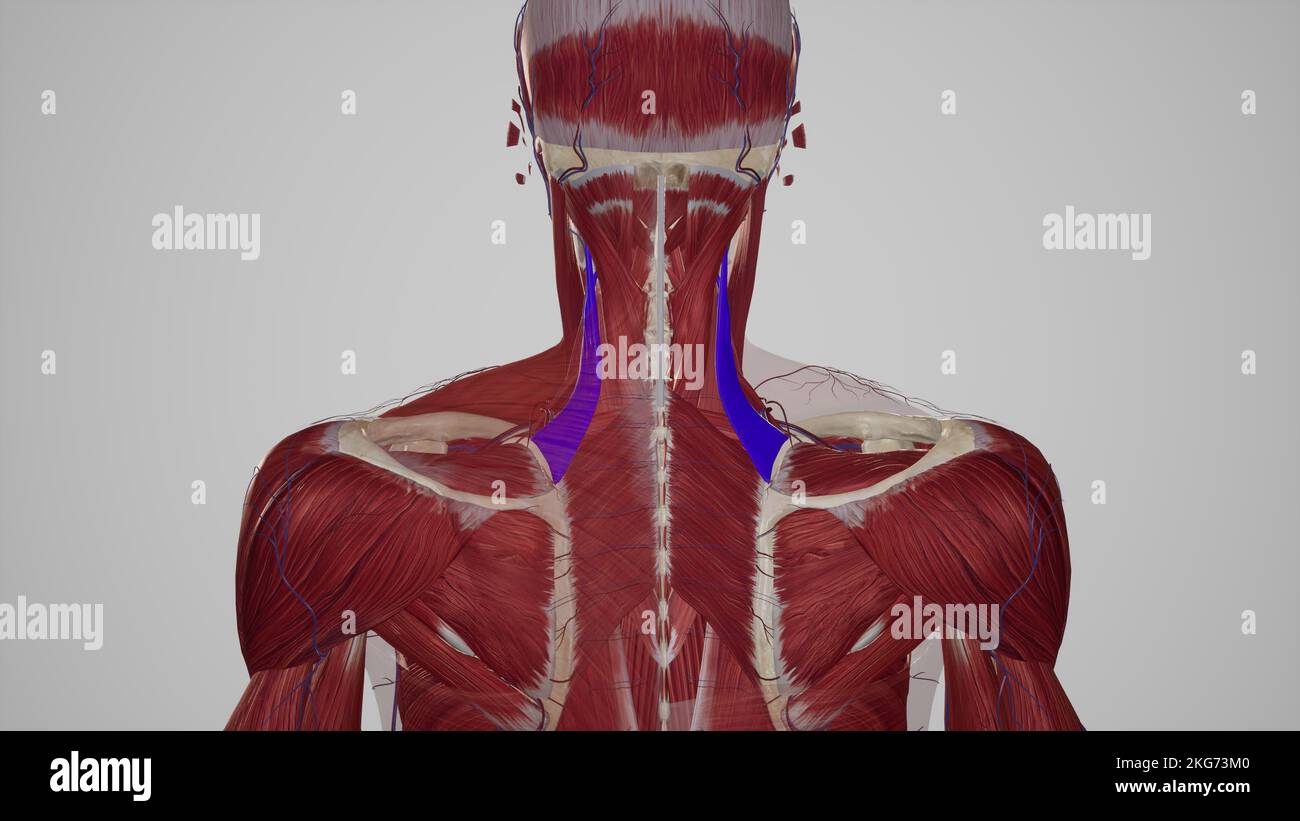

RF2H35542–Frattura della spalla radiogena metà posteriore del glenoide con dislocazione posteriore del frammento osseo. Frattura trasversale irregolare nel corpo della scapola.

RF2WA30RC–Radiografia semplice che mostra frattura dell'omero sinistro dell'albero intermedio trasversale causata da un trauma diretto in un incidente stradale, gestito da riduzione aperta e fissa interna

RF2GCN749–La vista scout (topogramma) per una TC dell'addome e del bacino con contrasto endovenoso. Immagini di riferimento per l'acquisizione di una serie TC assiale.

RF2WA2Y85–Radiografia semplice che mostra frattura dell'omero sinistro dell'albero intermedio trasversale causata da un trauma diretto in un incidente stradale, gestito da riduzione aperta e fissa interna

RF2W9YWMX–Radiografia semplice che mostra frattura dell'omero sinistro dell'albero intermedio trasversale causata da un trauma diretto in un incidente stradale, gestito da riduzione aperta e fissa interna

RF2W9YW6Y–Radiografia semplice che mostra frattura dell'omero sinistro dell'albero intermedio trasversale causata da un trauma diretto in un incidente stradale, gestito da riduzione aperta e fissa interna

RF2W9YWN6–Radiografia semplice che mostra frattura dell'omero sinistro dell'albero intermedio trasversale causata da un trauma diretto in un incidente stradale, gestito da riduzione aperta e fissa interna